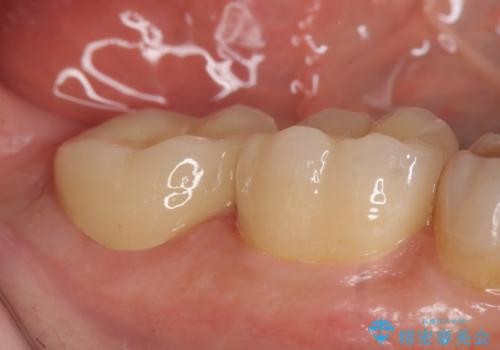

- 昔治療した奥歯の見た目が気になるのでセラミックでやり直したいといらっしゃった方の症例です。

右下6、7の古い詰め物および虫歯を除去後、オールセラミッククラウンによる補綴を行いました。

今回用いたオールセラミッククラウンはジルコニアフレームという白い素材の上にセラミックを盛っているため、審美性が非常に高いのが特徴です。

また、ジルコニアは人工ダイヤモンドの材料にも使われているほど高い強度を持っており、そのためオールセラミッククラウンは審美性だけでなく、奥歯やブリッジの補綴も可能とするクラウンです。